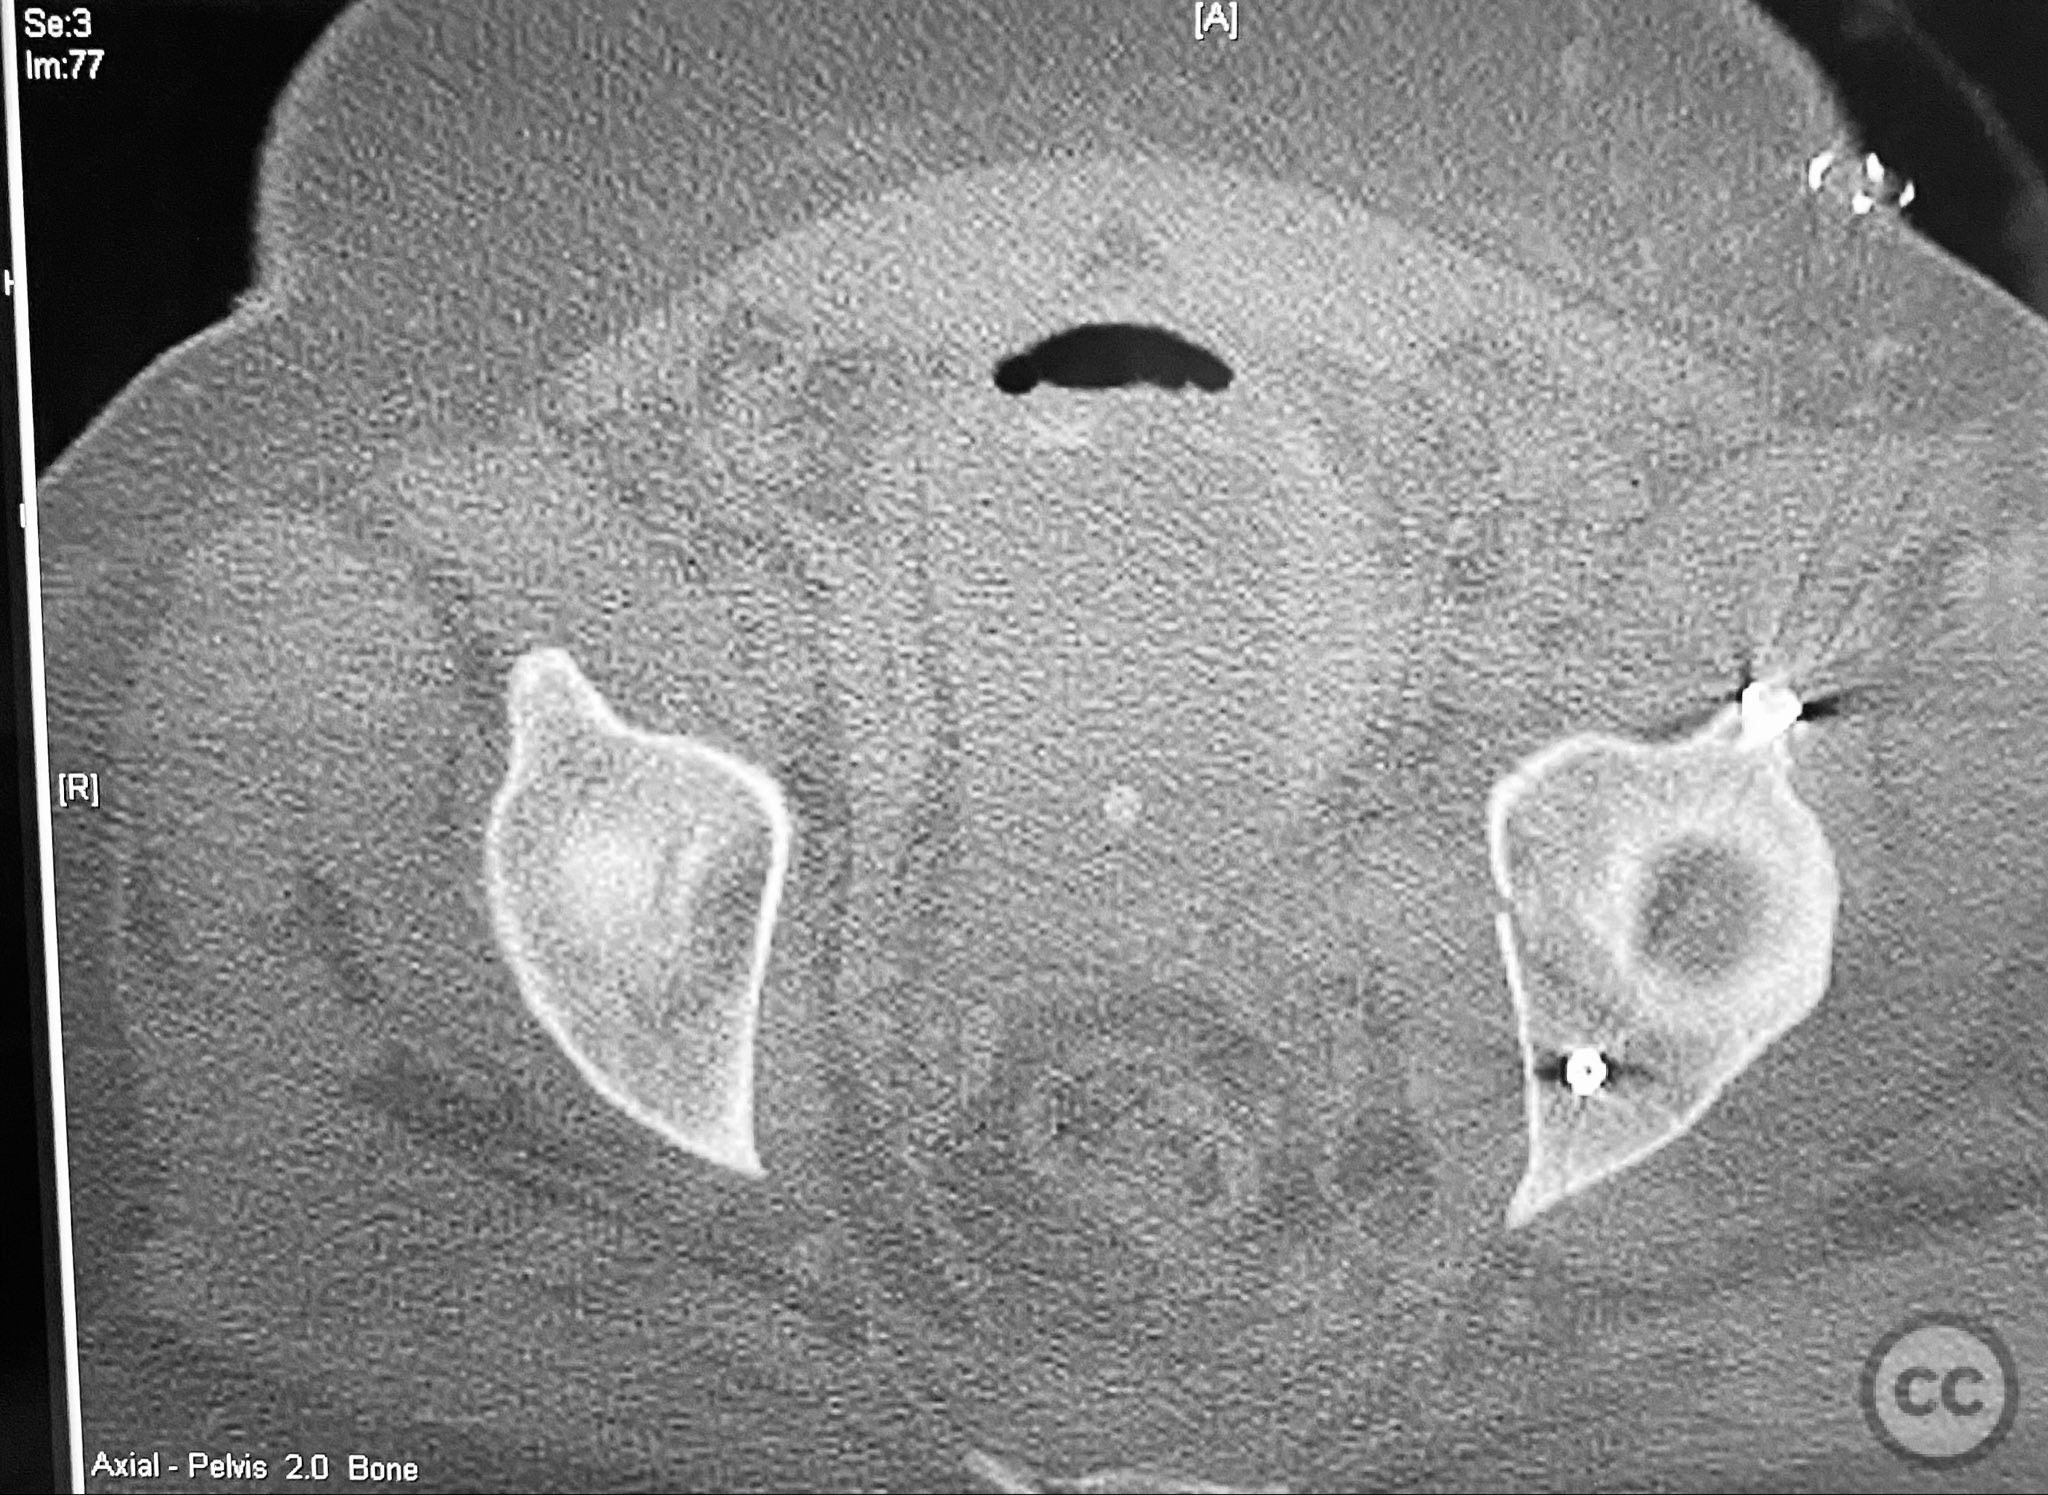

Clinical and radiological findings:  A patient presented with a displaced associated both column acetabular fracture, characterized radiographically by the presence of the "spur sign" on the anteroposterior (AP) pelvis film, indicating the caudal aspect of the intact ilium exposed by medial displacement of the articular fragments. The spur was more clearly visualized on the obturator oblique rendered image. Axial computed tomography (CT) images demonstrated the intact ilium, medially displaced anterior column (AC) and posterior column (PC) fragments, and provided detailed visualization of surrounding soft tissues, including vascular structures enhanced by contrast. Multiplanar CT reconstructions (axial, sagittal, coronal) and 3D renderings were utilized for comprehensive fracture and soft tissue assessment. The patient’s overall clinical condition was a significant factor in surgical planning.

The operative sequence was dictated by the patient’s overall clinical status, necessitating staged management. Intraoperative attention was paid to implant placement during AC fixation to preserve access for subsequent percutaneous PC fixation. Postoperative CT confirmed satisfactory reduction and fixation of both columns, with appropriate implant positioning and no evidence of neurovascular compromise or significant soft tissue complications.